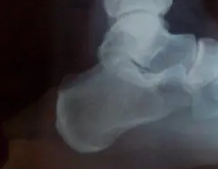

后脚跟痛是什么原因怎么治疗?

脚后跟疼痛,我们医学上又叫跟痛症,也有人叫足跟痛,其实就是跖筋膜炎。跟痛症的发病原因有几种…「查看详情」

足跟痛的症状及危害

足跟部疼痛。主要为跟部疼痛为主,时而可牵扯小腿后侧疼痛,病起缓慢,早晨起床下地足跟痛,稍走动后缓解,行走较多,疼痛又明显,严重时影响走动。…「查看详情」

跟腱炎都会有哪些临床症状表现

跟腱炎是一种常见的骨科疾病,跟腱炎是指跟腱发生了炎症。一般来说,它是因为在运动过程中,小腿腓肠肌和跟腱承受了太大的压力导致的。引发跟腱炎很容易引发一系列的并发症,严重影响…「查看详情」